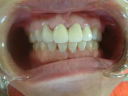

初診の状態とセット時の状態